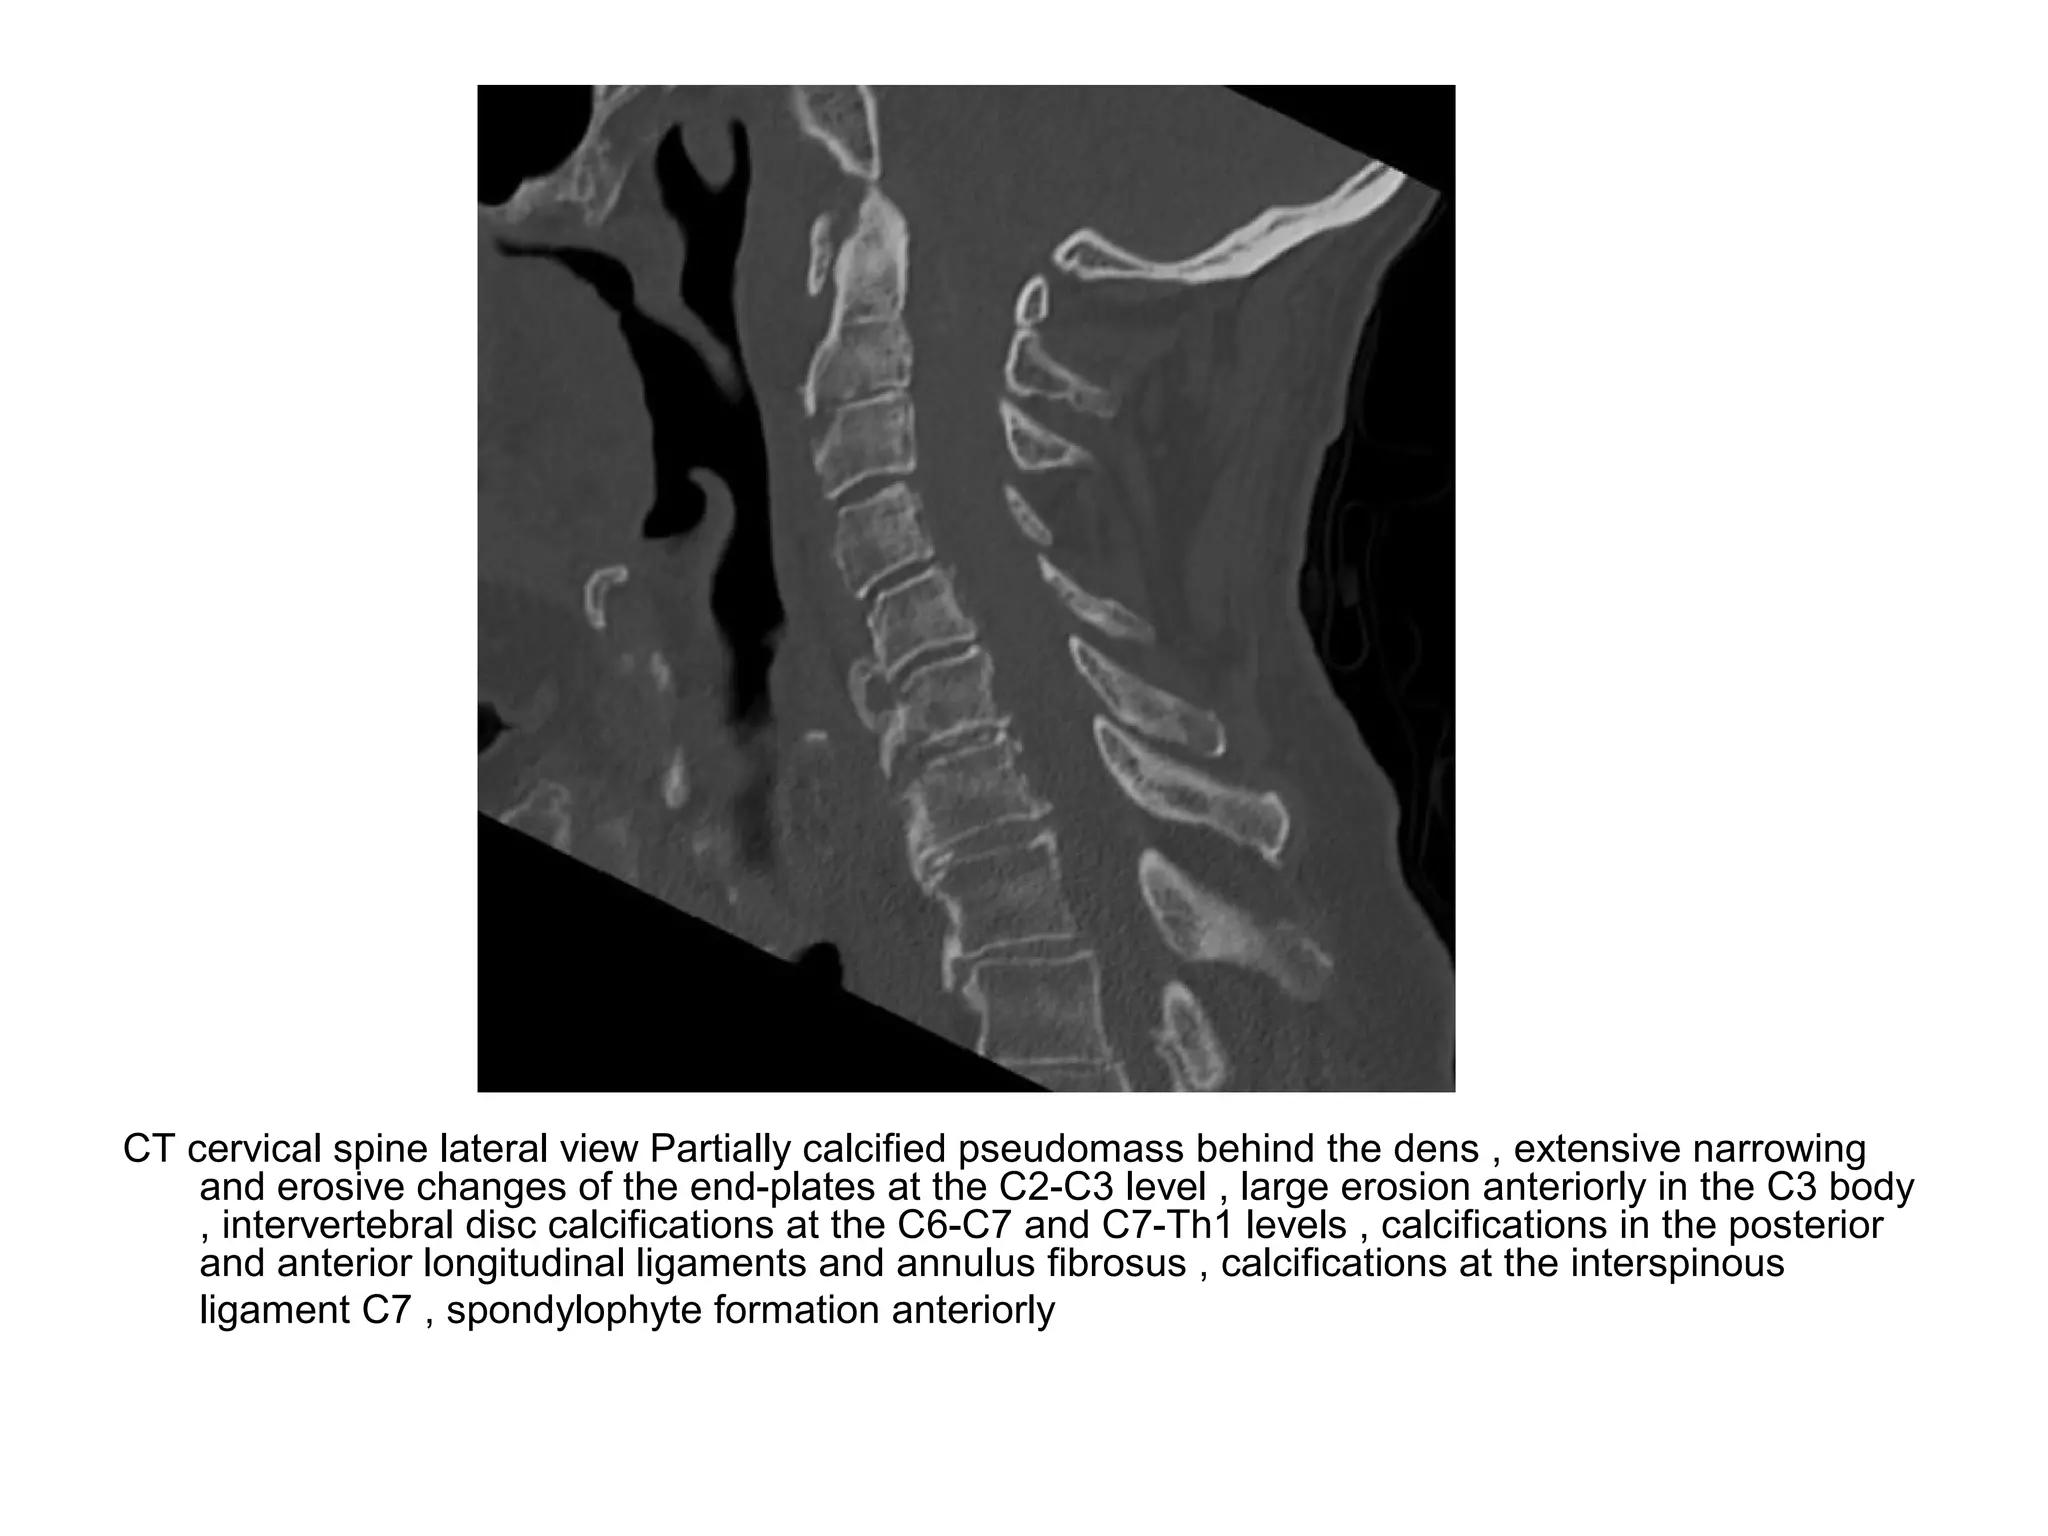

Cervical spine Narrowing of all disc spaces especially at the C2-C3 level with a marginal

erosion anteriorly and irregular lining of the end-plates , calcifications of the anterior

longitudinal ligament and spondylophyte formation anteriorly

CT cervical spine lateral view Partially calcified pseudomass behind the dens , extensive narrowing

and erosive changes of the end-plates at the C2-C3 level , large erosion anteriorly in the C3 body

, intervertebral disc calcifications at the C6-C7 and C7-Th1 levels , calcifications in the posterior

and anterior longitudinal ligaments and annulus fibrosus , calcifications at the interspinous

ligament C7 , spondylophyte formation anteriorly